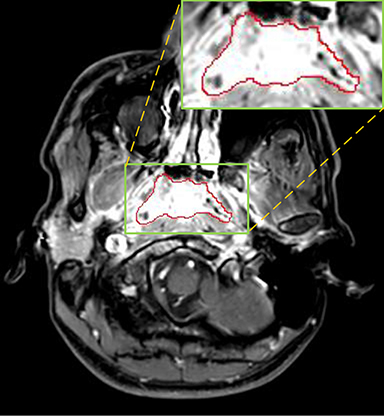

Currently, there is still no effort to fuse multi-modality MRI to develop an automatic segmentation system for NPC. According to researches of Popovtzer et al. [16], it should be a routine clinical practice to incorporate all kinds of MRI datasets in highly conformal radiation therapy to realize GTV delineation of NPC. For delineation of NPC, MRI is the perferred imaging modality for its superior soft tissue contrast [16, 3]. Moreover, MRI of different modalities data have different visual characteristics and various responses to different tissues and anatomical structures. For example, T1-weighted (T1) MRI is suitable for detecting skull base involvement and fat planes, while contrast-enhanced T1-weighted (CET1) MRI is used to identity tumor extent [3]. Figure 1 shows some examples of NPC response in T1, CET1 and T2-weighted (T2) MRI.

Refer to caption

Figure 1: Examples of slices from different MRI (T1, CET1 and T2), the contour of NPC is marked in red line. (a),(b) and (c) are slices from T1 , CET1 and T2 respectively.